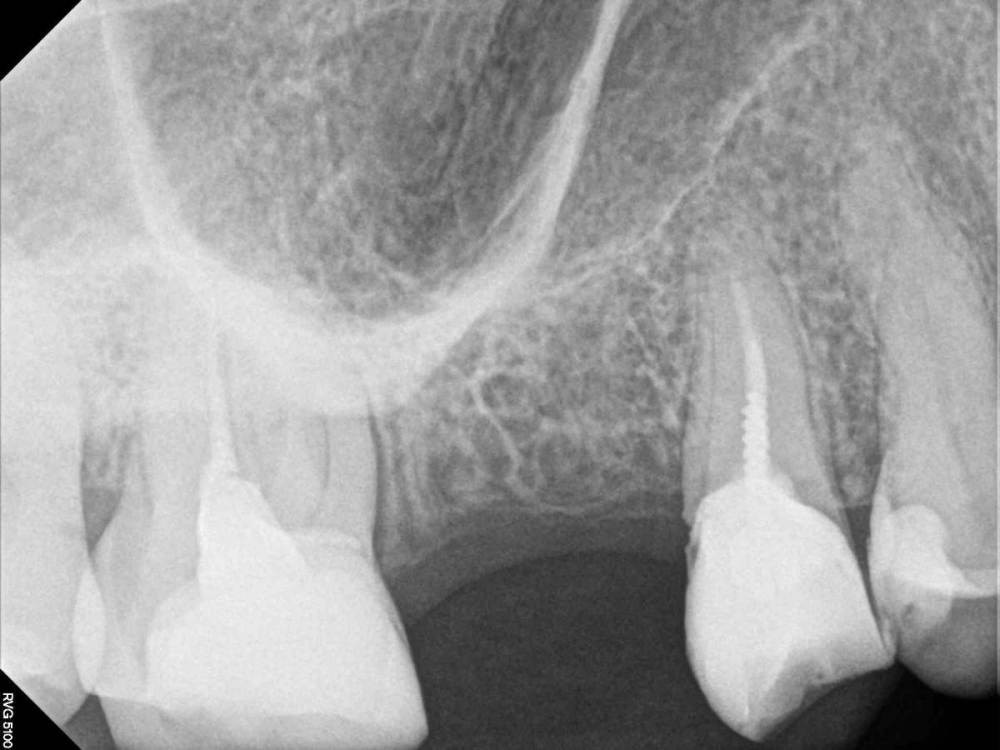

ElenaN Опубликовано 27 апреля, 2021 Поделиться Опубликовано 27 апреля, 2021 (изменено) Есть ли отверстие (перфорация) между гайморовой пазухой и ротовой полостью СПРАВА вверху после удаления 6 верхнего зуба?? Как на ваш взгляд? Одни врачи срочно посылают на операцию на основании только этого снимка, другие говорят, что дырки нет, пазуха спокойна и не нужно ничего трогать, чтобы не было хуже. Посмотрите, пожалуйста, что за ситуацию вы видите? Чтобы не перепутать с левой (здоровой) стороной - под больным местом снизу зуба тоже нет. Проблема - СПРАВА (около левой стороны написано "L"). 16.10.2020 удалили 6-ку сверху справа, боль совсем не проходит уже 7 месяцев. Только на 4-м по счёту панорамном снимке от 16.04.2021 (прикреплён) уже в другой клинике нашли перфорацию гайморовой пазухи при удалении зуба (There was an OAC present intraorally). Рекомендация - операция как можно быстрее, чтобы закрыть отверстие. Показать мне на снимке, где именно нашли отверстие, доктора отказались. Обратилась к другому врачу - он никакого прободения не видит. Говорит, что после операции может быть только хуже. Нужно искать другую причину боли. Пожалуйста, посмотрите. Мучаюсь от боли уже 7 месяцев. На вторую врачебную ошибку не готова. Не в России, из-за карантина не могу добраться до специалистов. Буду благодарна за любые версии. Других признаков сообщения с пазухой нет: могу надуть щёки, из носа ничего не бежит, пища в нос не попадает, плохо не пахнет, запахи все чувствую, как раньше, голос не менялся и т.п. Боль на месте удаления, концентрируется вдоль пятого зуба уходит вверх, от 3 до 10 по шкале до 10. Боль постоянная, фоновая, резкой, чтоб подскакивала, не бывает. Если удаётся уснуть - не просыпаюсь. Десна над местом удаления около 5 чувствительна, кость над местом удаления реагирует на горячее больше, на холодное меньше. К щеке прикасаться неприятно, в пазухе иногда свербит. Что-то в этом месте неправильно и нехорошо. За 7 месяцев потихоньку схожу с ума. Но есть ли дырка? Нужна ли операция? И насколько срочно? Изменено 27 апреля, 2021 пользователем ElenaN опечатка Ссылка на комментарий

Irouil Опубликовано 27 апреля, 2021 Поделиться Опубликовано 27 апреля, 2021 (изменено) По предоставленному снимку точно сказать что-то о наличии перфорации (а если речь идёт о 7 месяцах - стойком соустье) нельзя, но очень вероятно что ее там нет - в месте удаленного зуба все выглядит абсолютно нормально. Да и вся описаная симптоматика на соустье не тянет никак. Есть зубы справа, которые точно нуждаются в санации - это и 5, и 7, и 8 сверху, а так же 5 и 8 снизу. Теоретически, любой из них может быть виновником подобных болей, но самый вероятный кандидат - верхняя 8-ка. Если санация зубов не даст результата - провести диагностику ВНЧС и неврита 2-й ветви тройничного нерва. Очень рекомендую сначала провести КЛКТ исследование челюстей с захватом хотя бы верхнечелюстных пазух P.S. Судя по приведённой формулировке, ОАС Вам диагностировали не по снимку, а при осмотре в полости рта (intraorally), а это - приоритетный источник информации Изменено 27 апреля, 2021 пользователем Irouil 2 Ссылка на комментарий

ElenaN Опубликовано 28 апреля, 2021 Автор Поделиться Опубликовано 28 апреля, 2021 (изменено) 15 часов назад, Irouil сказал: P.S. Судя по приведённой формулировке, ОАС Вам диагностировали не по снимку, а при осмотре в полости рта (intraorally), а это - приоритетный источник информации Спасибо. Там полная формулировка такая: "On examination in the upper right malar region extraorally was some tenderness. There was no swelling but there was some tenderness on the rigth hand side. There was an OAC present intraorally which can be probed 3,5mm and the OAC was visible on the OPG. We have planned for her to have this closed under local anaesthetic". И есть ещё такой более ранний снимок (от марта). @annda Спасибо. Изменено 28 апреля, 2021 пользователем ElenaN Добавила информацию Ссылка на комментарий

Irouil Опубликовано 28 апреля, 2021 Поделиться Опубликовано 28 апреля, 2021 Честно говоря, зондирование на 3.5 мм в глубину мало о чем говорит - в конце концов, зачастую только толщина слизистой полости рта может составлять более 3 мм. По второму снимку, как и по первому, никаких признаков наличия ОАС я не отмечаю Я соглашусь с @anndaчто более всего описанная симптоматика похожа на неврологию, но я сразу хочу предупредить, что многие неврологи могут сначала отправить Вас на санацию полости рта, чтобы исключить влияние любой зубной патологии. 1 Ссылка на комментарий

annda Опубликовано 28 апреля, 2021 Поделиться Опубликовано 28 апреля, 2021 Пародонт у щечномедиального корня 6ки не очень выглядит, трещину бы исключить.Но такой пародонт и от перегрузки может быть.И жалобы на трещину не тянут. 1 Ссылка на комментарий

annda Опубликовано 28 апреля, 2021 Поделиться Опубликовано 28 апреля, 2021 Пардон, 7ка, обсчиталась 1 Ссылка на комментарий